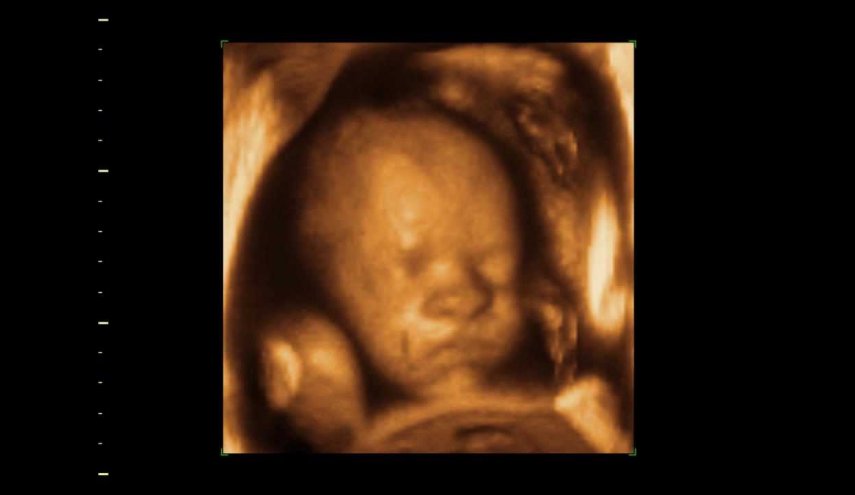

وأشارت المراهقة إلى أن الطبيبة التي كانت معها خلال جلسة التصوير بـالموجات فوق الصوتية، أخبرتها أن طفلتها طبيعية وبحالة جيدة، لافتة إلى أنه من غير الغريب أن يظهر الجنين بهذا الشكل في الصور.